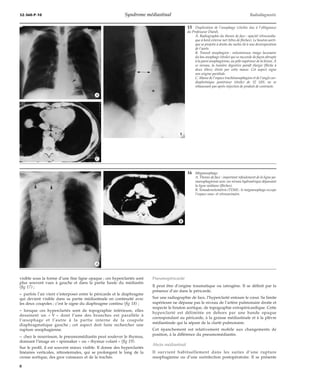

14 Spondylodiscite tuberculeuse de T6.

A. Thorax de face : déplacement des lignes paravertébra-les

(têtes de flèches) et érosion des plateaux de T6 et T7.

B. Tomodensitométrie (TDM) : masse des deux gouttiè-res

paravertébrales, de l’espace sous-carinaire avec exten-sion

dans le canal vertébral. Cette lésion est hétérogène

avec des plages hypodenses (étoiles) présentant un re-haussement

périphérique après injection intraveineuse

de contraste.

C. Imagerie par résonance magnétique (IRM) : coupe

frontale pondérée en T1 montrant l’atteinte vertébrale

et le signal iso-intense aux muscles.

D. IRM : coupe axiale transverse pondérée T2 montrant

l’hypersignal de l’abcès pottique (étoiles) différent

du faible signal des adénopathies sous-carinaires.

E. IRM : coupe sagittale médiane pondérée T2 montrant

l’extension dans l’espace extradural et le refoulement

du ligament vertébral commun postérieur (tête de flèche).